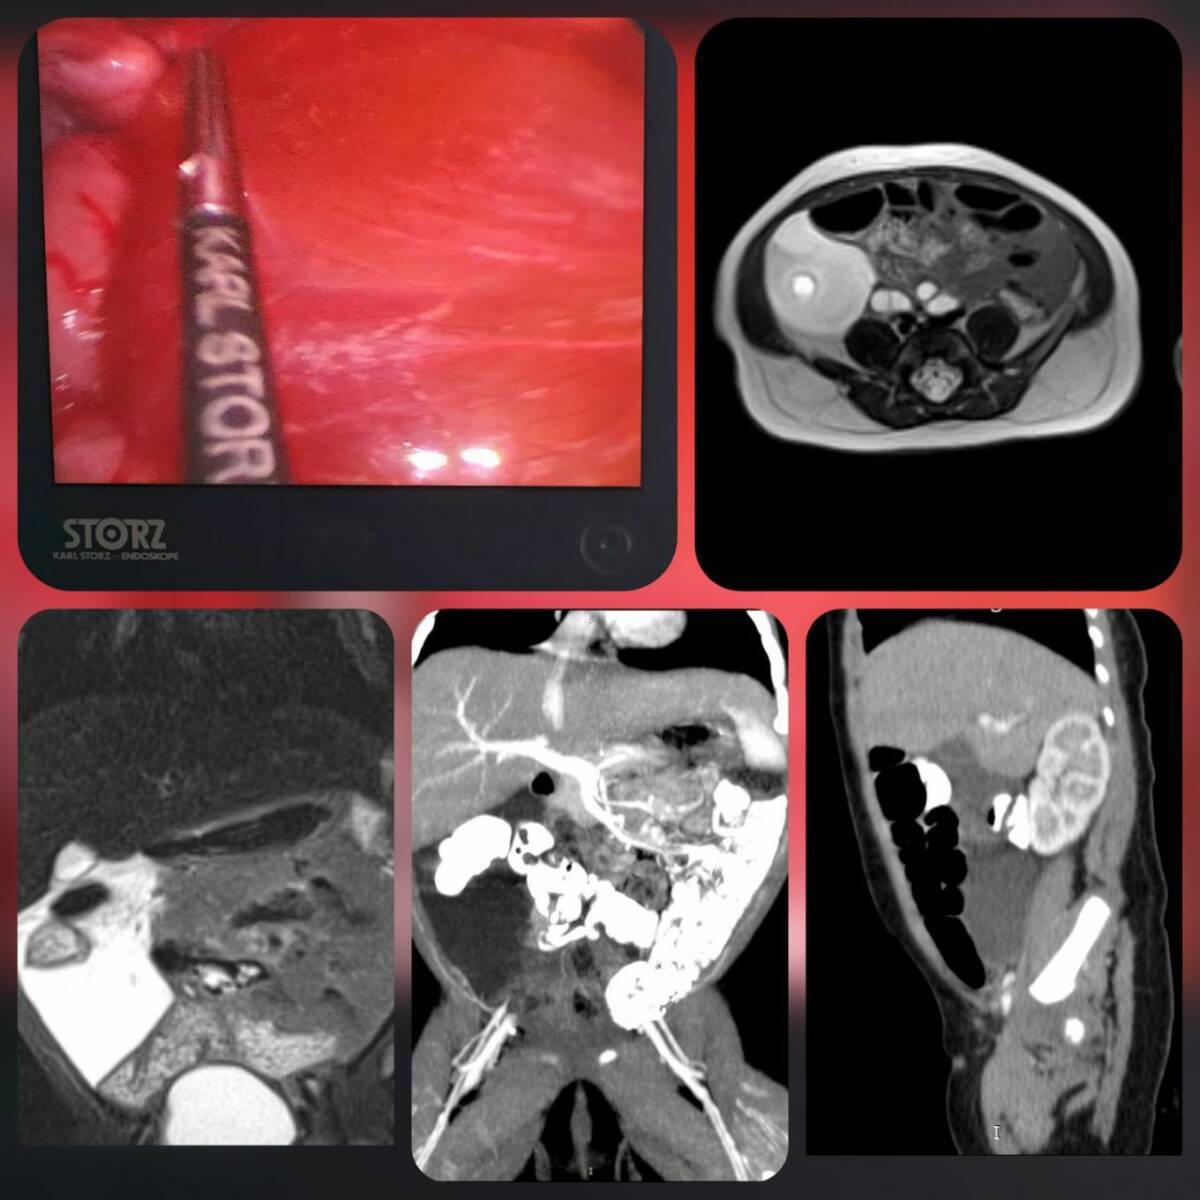

Ребенка срочно госпитализировали в отделение хирургии детей раннего возраста с крупным кистозным образованием в брюшной полости, которое выявили на УЗИ. После комплексного обследования специалисты подтвердили редкую аномалию развития лимфатических сосудов в брыжейке толстой кишки.

Хирурги Мария Зыкова и Буй Вьет Анх выполнили малоинвазивную операцию – лапароскопическое удаление лимфатической мальформации с сохранением сосудов брыжейки толстого кишечника. Чтобы предотвратить повторное появление заболевания, внутреннюю поверхность лимфатических кист обработали специальным раствором, формирующим полимерное покрытие, препятствующее образованию лимфы.

«Описанный случай является крайне редким. Чаще всего подобные образования обнаруживаются в области шеи и подмышечных впадин. По статистике, такие случаи встречаются примерно в 4 на 100 000 госпитализаций. Лечение крайне сложно из-за высокого риска осложнений: воспаления, перфорации, компрессии соседних органов и лимфоистечения», – объяснили в пресс-службе ДРКБ.